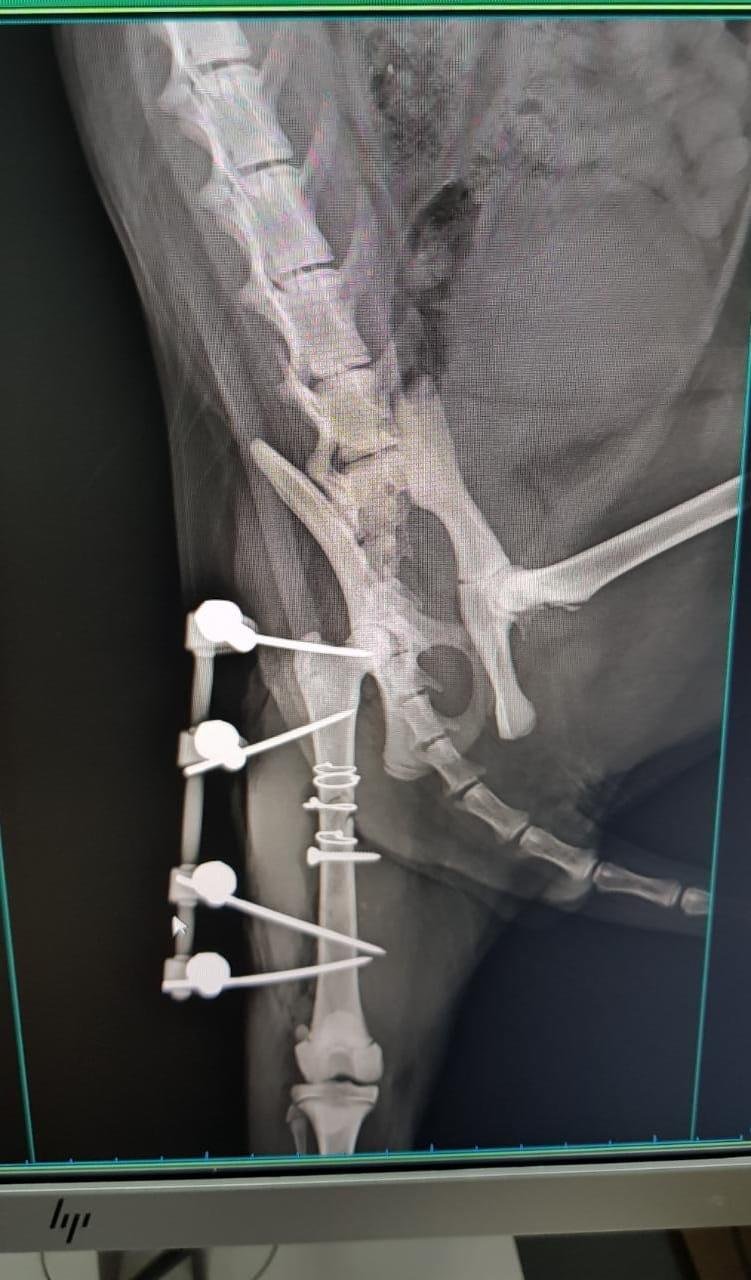

"Olá, Pessoal! Alguns de vocês já me viram pelas redes sociais e alguns já até se disponibilizaram em ajudar, mas eu fui atropelado, atendido de forma emergencial e passei por uma cirurgia bem complicadinha! Fraturei o quadril e quebrei meu fêmur! Mas fui muito forte, bonzinho e valente, além de ser um gatinho muito lindo e especial! Tudo isso custou até o momento R$ 1.440,00, fora medicamentos e outros gastos que poderei ter depois. Estou feliz e agradecido por ter sido socorrido pela minha nova Mamãezinha Lilian, mas contamos com a ajuda de todos que se comoveram com a nossa situação... desde que minha Mamãezinha tem dedicado todo o amor do mundo pra mim, mas não tem condições de pagar essa conta sozinha! Vocês poderiam nos ajudar, por favor? Pode ser com R$ 10 ou a quantia que puderem! Nós agradecemos muito e desejamos de coração que Deus abençoe a todos! Com muita gratidão, Valentin.”